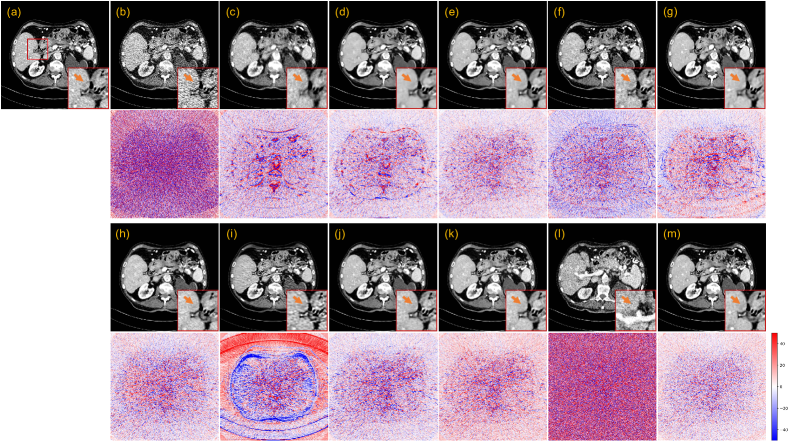

3.3.1 Evaluation on the 25% dose

Fig. 4 presents a representative slice of 25% dose test data denoised by different methods for visual comparison. The orange arrow indicates the location of the lesion in the red region of interest (ROI). Although the RED-CNN-based methods effectively remove noise from the LDCT image, it tends to blur fine details. Among the GAN-based methods, WGAN-VGG introduces velvet artifacts, and DU-GAN provides textures closer to NDCT images. CNCL-U-Net preserves the most details, but its residual map shows a noticeable difference in predicting the bone edge. Among the diffusion-based models, DDM2 exhibits obvious artifacts and CT number drift. We conjectured that this phenomenon may result from the fact that DDM2 assumes the image noise adheres to a Gaussian distribution, which deviates from the actual noise distribution of CT images. Both in terms of texture preservation and detail retention, IDDPM and our CoreDiff surpass other compared methods. For the IDDPM, lowering the number of sampling steps to 50 has little impact on the denoising performance. However, when is reduced to 10, the model produces the poorest results due to much insufficient sampling. In addition, IDDPM-1000/-50 erase the critical lesion information, while our CoreDiff retains them well. The residual map confirms that our approach has the least prediction bias.

Fig. 5 presents the qualitative results of 5% dose test data. In this ultra-low dose scenario, the FBP image suffers from significantly severe noise and streak artifacts due to the photon starvation effect, making it unacceptable for clinical diagnosis. The denoising performance of some denoising methods has a sharp decline. Fig. 5 shows that RED-CNN-based methods and CNCL-U-Net produce over-smoothed results. In addition, both PWLS and WGAN-VGG introduce noticeable artifacts to the denoised images. The DU-GAN obtains the best performance besides the diffusion-based methods. However, the denoising result of DU-GAN shrinks the lesion size. Other diffusion-based models, except for IDDPM-10 and DDM2, consistently exhibit remarkable performance in ultra-low-dose denoising tasks, showing great promise for LDCT denoising. Among them, our CoreDiff exhibits the best denoising performance both in terms of residual maps and zoomed-in ROIs. Furthermore, Fig. 6 shows the profile results of the different methods, as indicated by the blue line in the NDCT images in Fig. 5. The red arrow indicates that our CoreDiff maintains the CT number better than other methods.